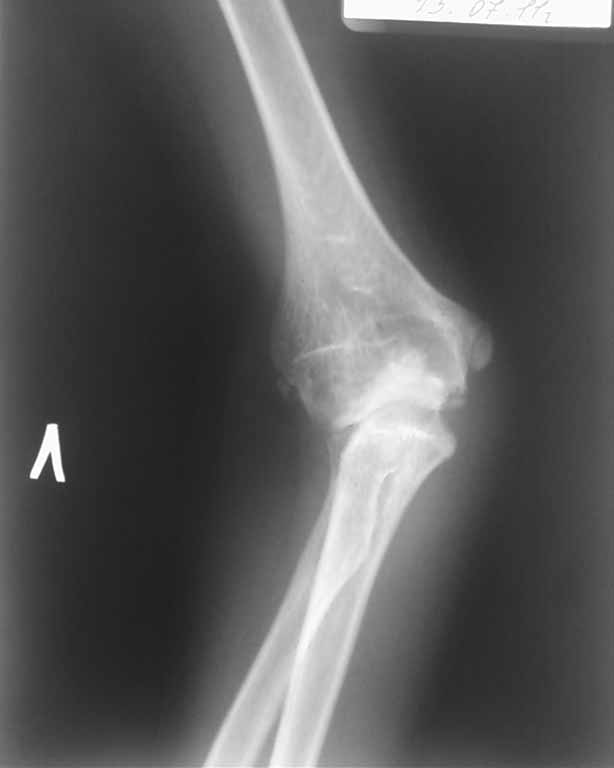

Снимок в боковой проекции не получилось сразу отправить.

Ответ собственно на все вопросы на боковой рентгенограмме: вывих лучевой кости. Либо перенесенный недиагносцированный-нелеченный Монтедж (повреждение Монтаджа: вывих лучевой кости с переломом локтевой кости). Более редкий вариант (скорее всего выявили бы раньше - врожденный вывих лучевой кости. Но честно говоря патология крайне редкая, да и не очень похоже.

Присмотрелся к боковой рентгенограмме сейчас... А можно повторить снимки в более стандартных укладках? А то складывается ощущение полного вывиха костей предплечья... Или это шутка укладки... Все-таки 7 лет жить с вывихом в локтевом суставе как-то нонсенс... Или все совсем запущено и предыдущий пост отменяется.

Клинически: отмечается вальгусная деформация локтевого сустава 32º, передневнутренний вывих головки лучевой кости. Разгибание 175º, сгибание 82º.

На рентгенограмме. Нарушение пропорциональности дистальных структур плечевой кости не отмечается. Объемная деформация головки лучевой кости не визуализируется, отмечается передневнутренний вывих головки лучевой кости. Отмечается нарушение сферичности локтевой вырезки, объемный дефицит суставной поверхности, который привел к объемному конфликту в плечелоктевом суставе, став причиной ограничения сгибания. Гипертрофия венечного отростка, увеличение ширины локтевого отростка в боковой проекции. Все эти изменения свидетельствуют о перенесенном переломе в области локтевого отростка.